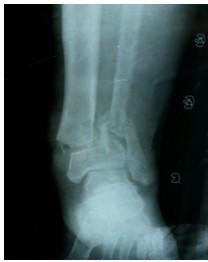

Se trata de un paciente masculino de 49 años de edad, con antecedentes de hipertensión arterial, atendido en el Hospital Gustavo Aldereguía Lima, de Cienfuegos, tras haber sufrido una caída desde una altura, que le produjo una fractura abierta tipo 2 de Gustillo-Anderson (Figura 1) y que se pudiera clasificar además como una fractura A3 según la fractura extrarticular con conminución metafisaria (AO/OTA). (Figuras 2 y 3).

Al recibir al lesionado se realizó su completa evaluación con el objetivo de determinar las posibles lesiones asociadas. Se indicaron todos los exámenes complementarios preoperatorios tales como Hb, Tc, Ts, Glucemia. Se realizaron rayos X de tórax anteroposterior, electrocardiograma, ultrasonido de abdomen y las radiografías anteroposterior y lateral del tercio distal de la tibia derecha lesionada.